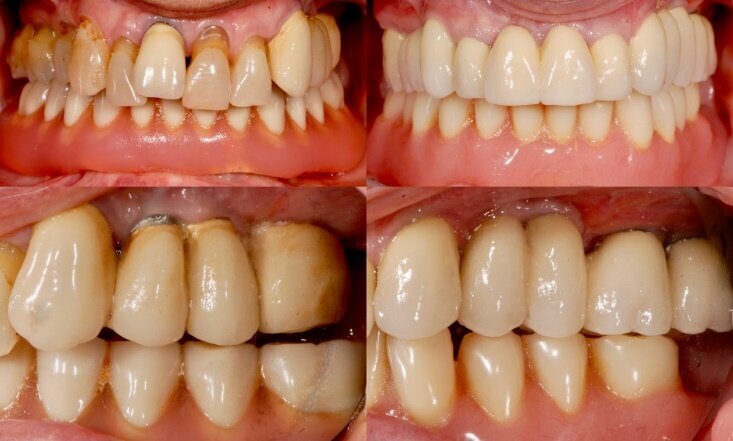

Fig. 7 - Confronto tra la condizione prima (sinistra) e dopo la riabilitazione (destra).